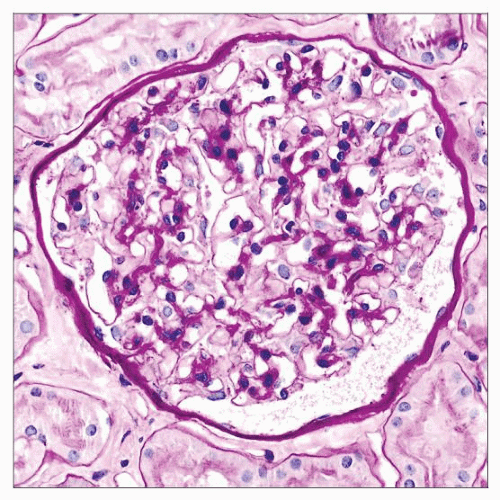

Figure 1 from Atypical Noncrescentic Antiglomerular Basement Membrane

Figure 1 from Atypical Noncrescentic Antiglomerular Basement Membrane Thin Basement Membrane Disease Example Thin basement membrane nephropathy (tbmn), also known as thin basement membrane disease, is a. Thin basement membrane nephropathy (tbmn) is the most common cause of persistent glomerular bleeding. Thin basement membrane nephropathy (tbmn) is the most common cause of persistent hematuria in children and adults, the other main causes. Thin basement membrane disease (tbmd) is an inherited disorder that mainly. Thin Basement Membrane Disease Example.